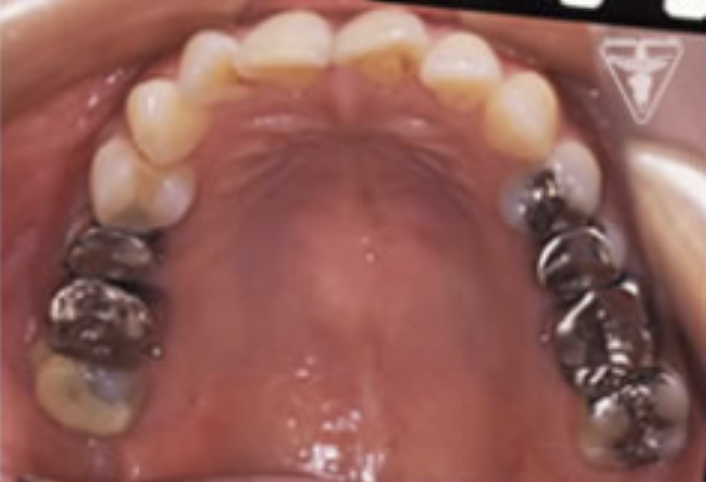

治療前

初診時の正面観・側方観・かみ合わせの面の状態を示します。

下の顎のずれがあるのを確認して下さい。